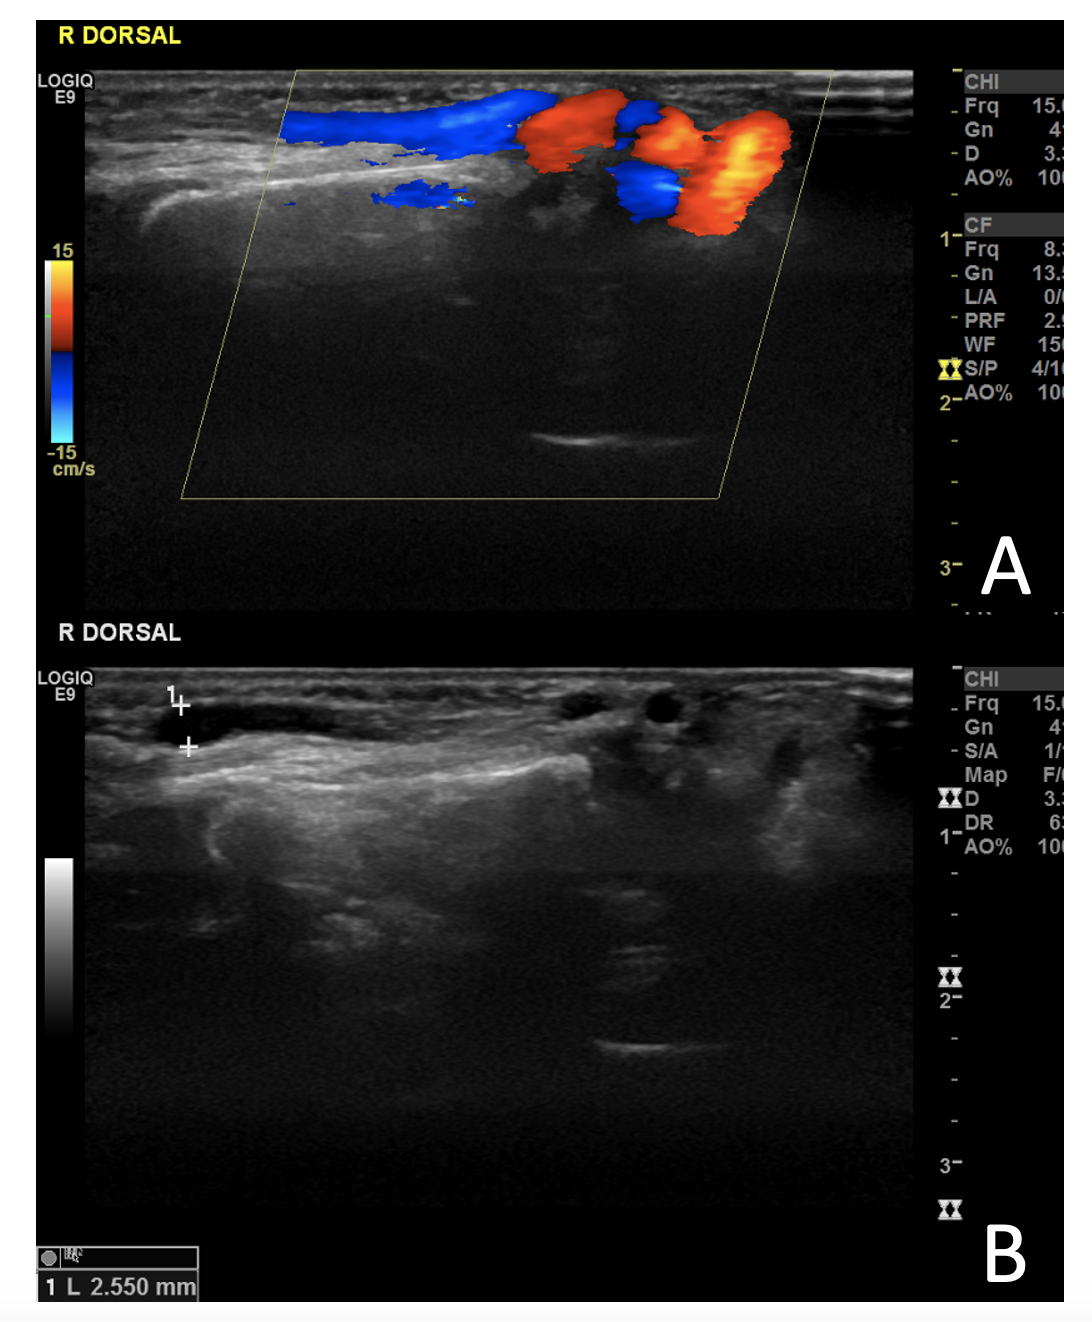

She was hospitalized for 23 days at her local hospital and 67 days at our hospital. Extensive liver investigations did not yield any significant cause, with spontaneous improvement of hepatic function. The karyotype, however, did show a mosaic of 45, XO, 46 XX. An ultrasound further elucidated the mass, which showed a communication between an artery and a vein (Figures 1 and 2).

The infant underwent an angiography. The ascending aorta was catheterized retrograde with the Seldinger technique. After preparation, the right femoral artery was accessed via a #4 sheath and a 4 x 1 Cobra catheter, a 4 x 2 pigtail, and a 0.035" guidewire (Video 1). The angiography showed an arteriovenous communication between the radial artery and cephalic vein over the right wrist. She was referred to surgery with a good operative result.

The main differential diagnosis is pseudoaneurysm formation.6 Arteriography in combination with ultrasound and Doppler studies can be utilized to delineate the anatomy and help guide optimal treatment.7-8 n